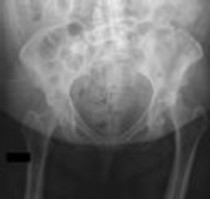

Question 2:

A 32-year-old male is brought to the trauma bay in hemorrhagic shock after a motorcycle crash. An anteroposterior radiograph of the pelvis demonstrates an APC-III injury. A pelvic binder is applied. To maximize reduction of the pelvic volume, at what anatomical landmark should the binder be centered?

Correct Answer: Greater trochanters

Explanation:

Pelvic binders should be centered over the greater trochanters to effectively close the pelvic ring and reduce pelvic volume. Placement over the iliac crests or ASIS can paradoxically widen the true pelvis or fail to achieve adequate reduction in an open-book pelvic injury.